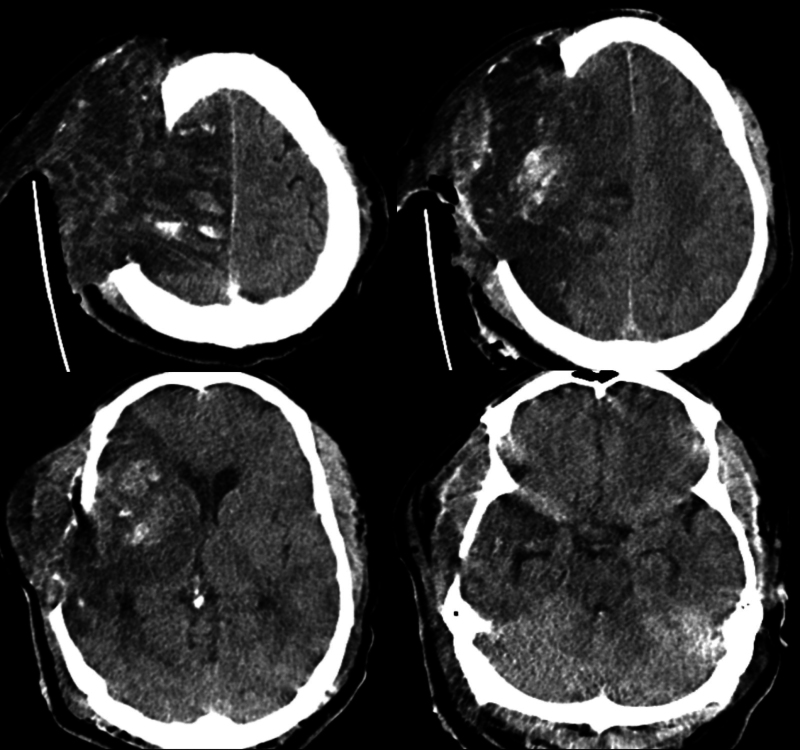

背景:恶性大脑中动脉(MCA)梗死导致脑水肿,可导致脑疝和死亡。标准治疗包括减压性半颅切除术(DHC)和综合神经危重症护理。尽管采取了这些措施,一些患者的病情仍会继续下降。重新开放头皮切口可能允许额外的减压,并提供死亡率的好处。观察:一名47岁男性在静脉溶栓和不成功的机械取栓后发生恶性右MCA区域梗死。尽管积极的高渗治疗和大DHC,患者继续表现出临床衰退和脑水肿的影像学进展。因此,重新打开头皮切口以促进最大程度的脑外疝,作者认为这是治疗脑肿胀的关键策略。在此期间,考虑到暴露的脑表面和潜在的脑脊液泄漏相关的感染风险增加,患者继续使用预防性抗生素。脑肿胀消退后,行右半球部分切除术切除梗死半球。值得注意的是,在干预和延长的康复期后,患者取得了显著的功能恢复。经验教训:本病例突出了恶性脑梗死手术治疗中遇到的复杂性,特别是当标准减压措施失败时。https://thejns.org/doi/10.3171/CASE2523。

Observations: A 47-year-old man developed malignant right MCA territory infarction following intravenous thrombolysis and unsuccessful mechanical thrombectomy. Despite aggressive hyperosmolar therapy and a large DHC, the patient continued to exhibit clinical decline and radiological progression of cerebral edema. In response, the scalp incision was reopened to facilitate maximal external cerebral herniation, a strategy the authors believe was critical in managing the brain swelling. The patient was maintained on prophylactic antibiotics during this period, given the increased infection risk associated with exposed brain surface and potential CSF leakage. Following the resolution of cerebral swelling, a right partial hemispherectomy was performed to excise the infarcted hemisphere. Notably, the patient achieved significant functional recovery following the intervention and an extended period of rehabilitation.